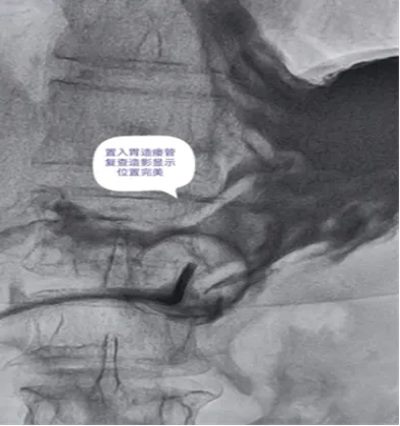

DSA引导下经皮胃造瘘术,是在数字减影血管造影(DSA)这个“透视眼”的实时可视化导航下,于患者腹壁上建立一个仅 3-5毫米 的微小穿刺点。通过这个“针眼”,医生精准地将一根营养管直接置入胃部,建立起一条直达的营养通道。

DSA影像全程清晰可视化,可精准避开血管、脏器等重要组织,穿刺定位误差小;穿刺创口仅3-5mm,出血量少,术后反流、误吸、肺炎等并发症发生率低于5%,术后1-2天即可正常喂养,恢复速度快。

医院临床实践中就有典型案例:一名65岁食道癌伴淋巴结转移患者,因食道狭窄无法插入胃镜,且体质虚弱难以耐受全麻手术,团队借助DSA精准导航,仅用10分钟便完成手术,局部麻醉下患者全程无明显不适,术后1天即可通过造瘘管补充营养,为后续抗肿瘤治疗顺利开展奠定了坚实基础。